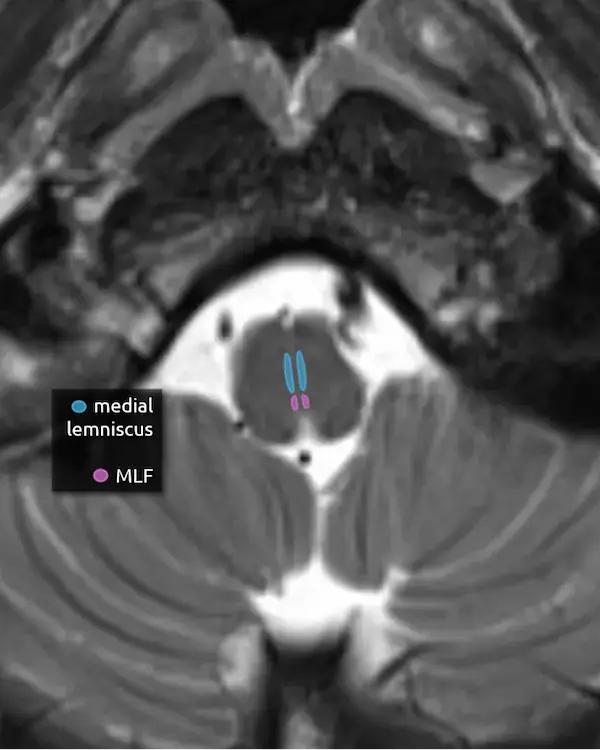

5. Medial lemniscus

The medial lemniscus is an ascending sensory pathway that spans the entire brainstem, originating at the nucleus gracilis and cuneatus (see level 5) in the medulla and ending at the primary sensory nucleus of the thalamus: the ventral posterolateral nucleus (VPL). It begins medially in the medulla and becomes more lateral at the level of the midbrain, located in close proximity to the substantia nigra. It is responsible for vibration sensation, fine touch, and proprioception.

Lesions involving the medial lemniscus may cause contralateral loss of vibration sensation and joint position sensation on physical exam with symptoms of numbness and paresthesias.

6. Medial longitudinal fasciculus (MLF)

The MLF is an ascending and descending pathway responsible for coordinating eye movements. It connects all of the cranial nerve nuclei that innervate the extraocular muscles (CN III, IV, and VI) as well as the vestibulocochlear nuclei (CN VIII). The MLF spans the entire brainstem, however lesions producing visual symptoms will probably be in the midbrain or pons.

There are characteristic syndromes that result from damage to the MLF, most commonly internuclear ophthalmoplegia (INO) or INO-plus syndromes. A common clinical scenario is a patient with multiple sclerosis who develops a demyelinating lesion along the MLF in the midbrain or pons and presents with bilateral INO.